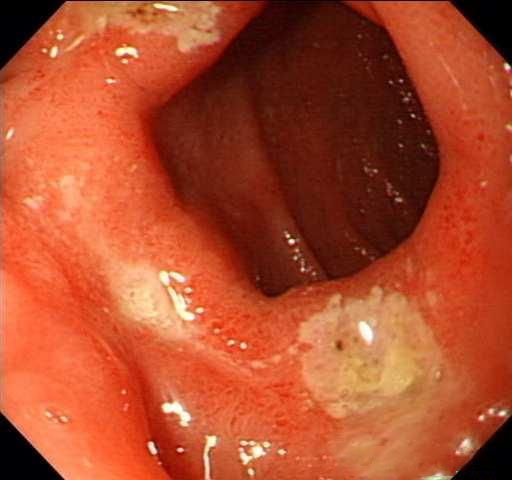

十二指腸炎怎么治療?

十二指腸炎注意保持生活、工作、飲食的規(guī)律性。養(yǎng)成良好的飲食及生活習(xí)慣,避免服用刺激性食物。抑酸治療??咕委?。也可通過對(duì)癥治療。中醫(yī)學(xué)者認(rèn)為原發(fā)性十二指腸炎主要由飲食不節(jié)、情志不調(diào)所致從治療上應(yīng)從肝、脾、胃來論抬。